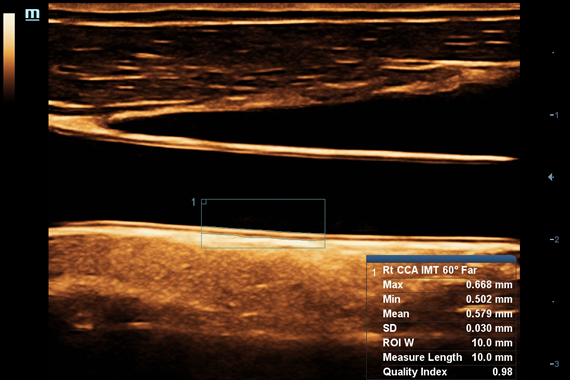

IMT (Intima Media thickness):

Да

Auto IMT+:

• Auto IMT Package – измерения и анализ толщины комплекса интимамедии (КИМ) сонной артерии